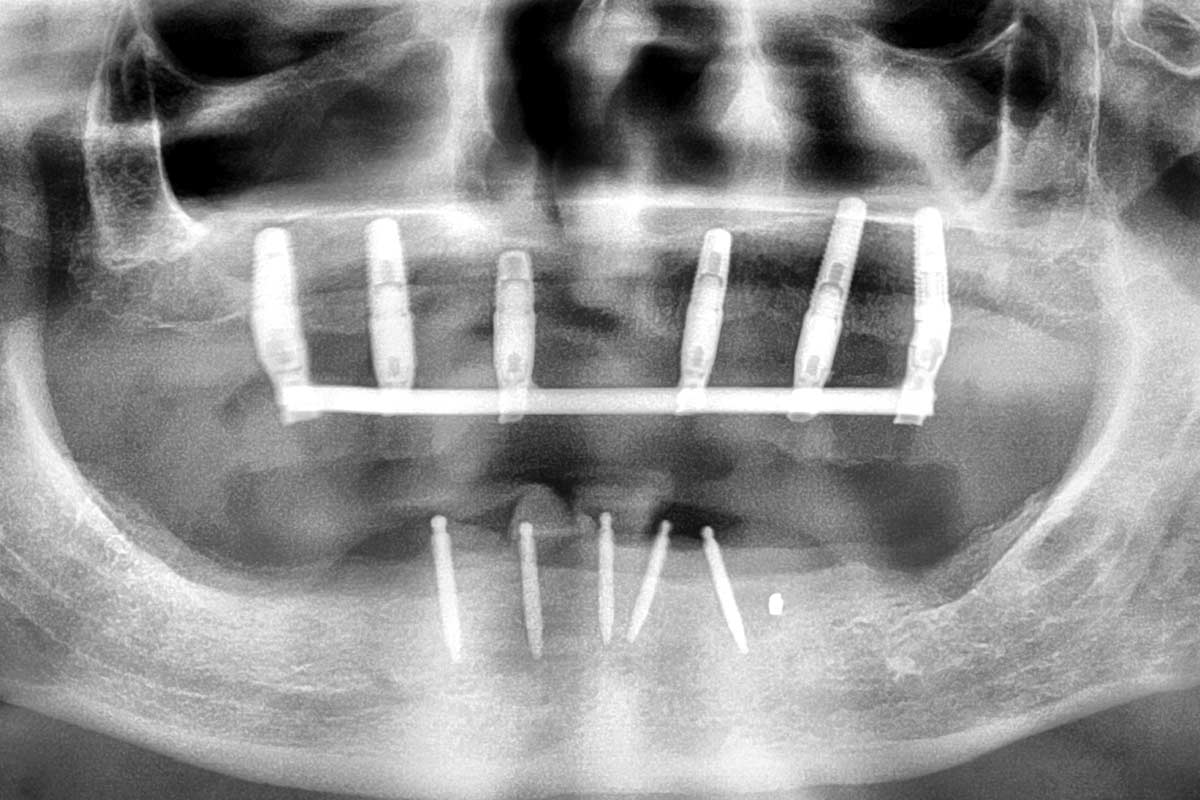

Ridge augmentation in the mandible with maxgraft® bonebuilder– Dr. R. Morger

Initial clinical situation: Free end situation in quadrant three and four